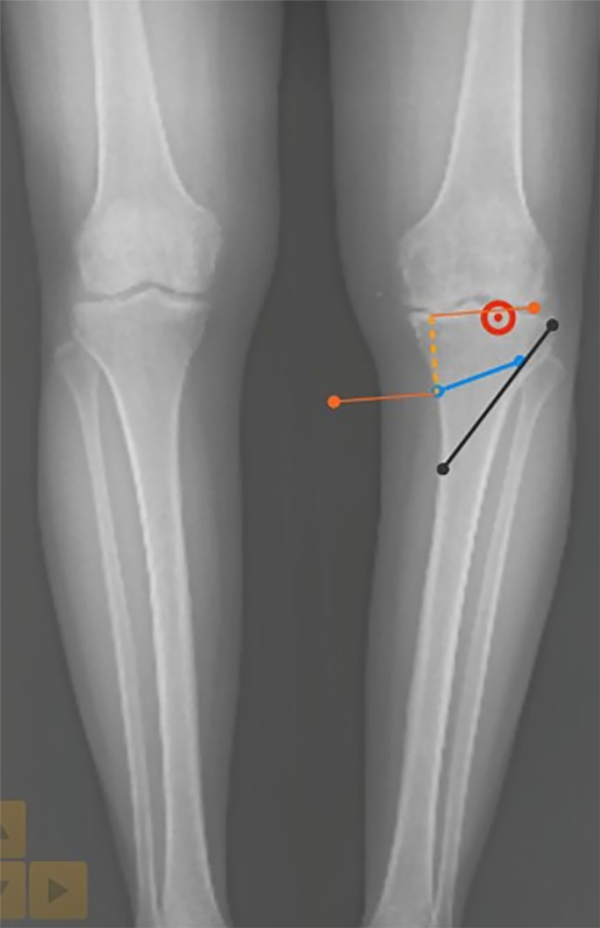

Trazar una línea correspondiente a la osteotomía: 4 cm distal a la superficie articular medial dirigida hacia la articulación tibioperonea proximal (línea azul de la fig. 27), esta línea va hasta 10 mm antes de la cortical lateral para obtener la longitud real de la osteotomía dejando espacio para el pin de protección de la bisagra (línea negra de la fig. 27).

Figura 27: Imagen correspondiente al Paso 4.